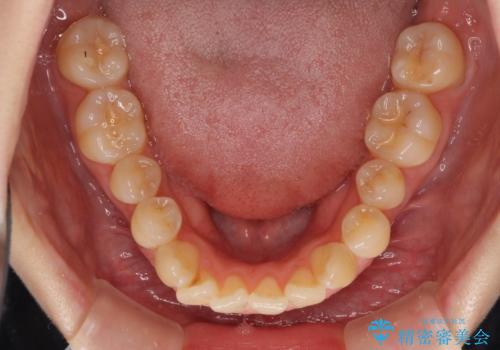

気になるデコボコとオープンバイト インビザラインでの矯正治療

- 前歯のデコボコと上下が開いていることを気にして来院された患者様です。

いわゆるオープンバイトは、インビザラインによる治療が適しているため、インビザラインにて治療を行うこととしました。

オープンバイトは容易に後戻りを起こすため、少しでも後戻りリスクを軽減するために舌癖改善のトレーニングをしっかりと行っていただきました。